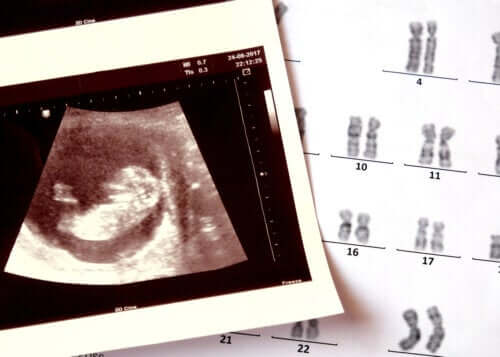

Des altérations chromosomiques (structures qui abritent tous les gènes dans les cellules) et certaines mutations ponctuelles pourraient contribuer à son apparition. Il a également été étudié que l’exposition à certaines toxines environnementales pourrait être déterminante. Bien qu’à l’heure actuelle les résultats des investigations ne soient pas concluants.